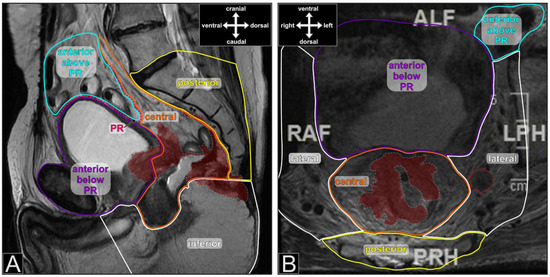

Figure 1. Pelvic MRI with delineation of the pelvic compartments (different colors, T2-weighted fast spin echo sequence). (A) sagittal image with a locally recurrent rectal cancer (anastomotic recurrence in a 68-year-old male) after anterior resection. The recurrent tumor is delineated with a grey dotted line and colored burgundy. PR—peritoneal reflection; (B) axial image with a cT3 primary tumor (marked as in A) and a positive lymph node in the left lateral compartment (red dotted line) in a 70-year-old male. The lymph node proved to be infiltrated by adenocarcinoma on histopathology after RCT and en bloc resection of the central and left lateral compartments.

The database of the colorectal unit of Dresden-Friedrichstadt General Hospital was queried for all consecutive patients with resection of rectal cancer infiltrating adjacent organs or exhibiting positive lateral lymph nodes (Figure 1B) that required en bloc resection of the lateral pelvic compartment (primary tumor group). Additionally, all patients operated on for a local recurrence of rectal cancer were retrieved (local recurrence group). The chosen time interval ranged from 2005 to 2019. Inclusion criteria were histologically confirmed adenocarcinoma, resection of either an adjacent organ or en bloc resection of one or both lateral compartments and attempt of complete tumor removal. Patients with histology other than adenocarcinoma or without an MRI of the pelvis were excluded. The extracted data were supplemented by an extensive chart review. We documented patient, treatment, and tumor characteristics. Additionally, initial MRI scans and reports were reviewed with respect to the extent of infiltration according to the seven compartments described by Georgiou et al. (Figure 1) [11]. If tumor infiltration was detected within the confines of one compartment, the compartment was judged infiltrated irrespective of the extent of infiltration. Investigators of the MRI scans were blinded against the pathology reports. Likewise, all histopathology reports were screened for the description of adjacent organ infiltration, and the declaration of compartment involvement followed the definitions of Georgiou et al. [11]. If a compartment was described as positive in MRI and negative in histopathology, the combination was judged as overstaging; likewise, if a compartment was negative in MRI and positive in histopathology, it was declared as understaging.